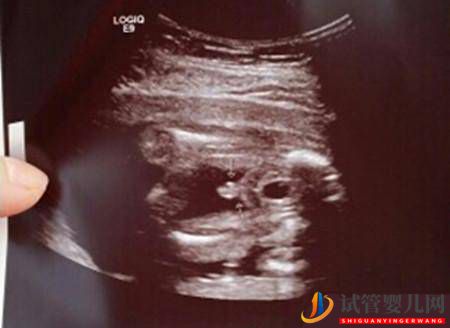

而且,虽然B超的确有小概率会出现误诊情况,但是胎儿的性别客观上是不会反转的——许愿也不会变的。